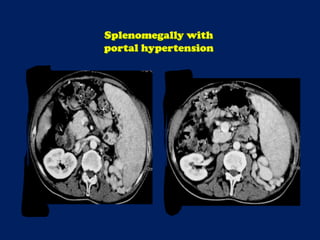

This document discusses imaging of the spleen and summarizes various congenital anomalies and pathologies that can affect the spleen. Some common congenital anomalies mentioned include accessory spleens, asplenia, polysplenia, and splenic fusions. Acquired conditions like repeated infarctions, infiltration, tumors, and cysts can also cause splenomegaly or functional asplenia. Wandering spleen is discussed as a rare congenital anomaly where the spleen lacks attachments and is mobile within the abdomen. Various grades of splenic lacerations and examples of splenic imaging findings are also briefly summarized.